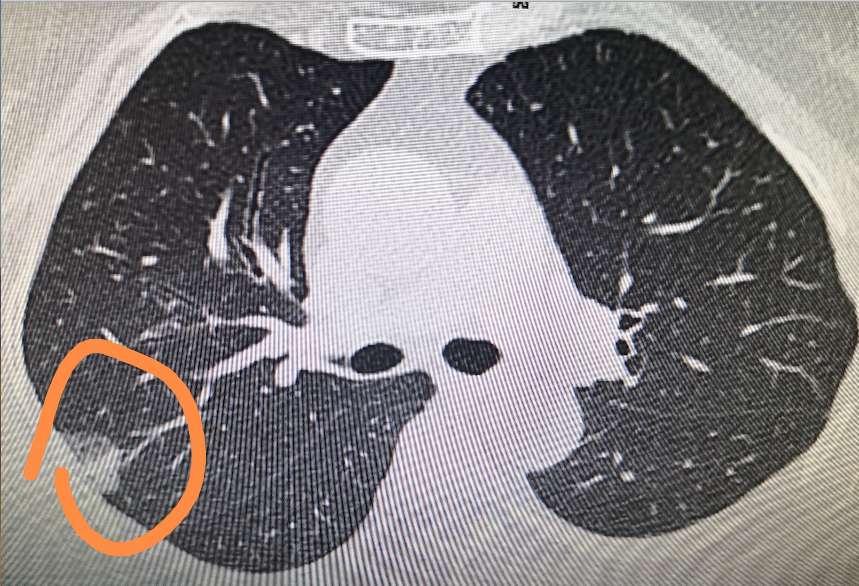

定期进行肺部检查是关注肺结节的重要方法之一。通过 X 光或 CT 扫描等检查手段,可以及时发现肺结节的存在及变化。

2.了解检查结果:认真解读检查报告,了解肺结节的大小、形态、位置等信息。